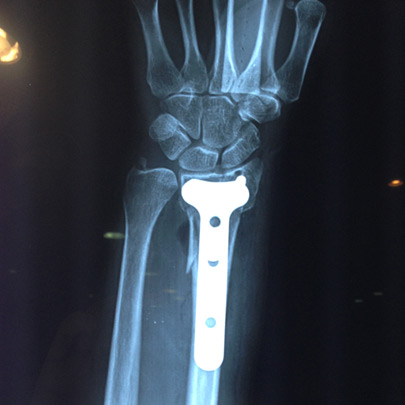

Fracturas y luxaciones

Tratamientos quirúrgicos